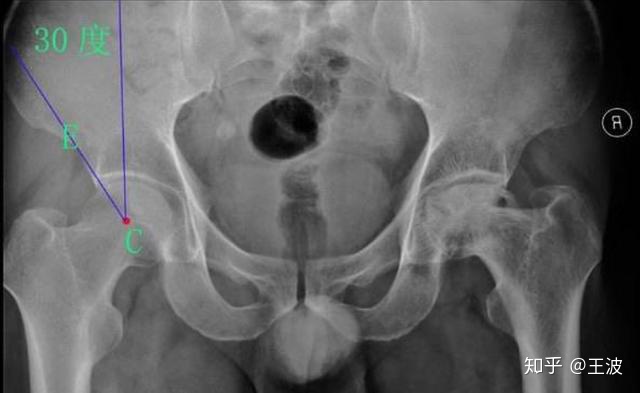

在正位X线片上,髋白发育不良主要表现为髋白发育浅小或浅平,股骨头的负重侧间隙增宽,并继发骨性关节炎。髋关节正位、蛙位X线片是了解与判断髋关节发育不良程度的最基础的影像学检查。